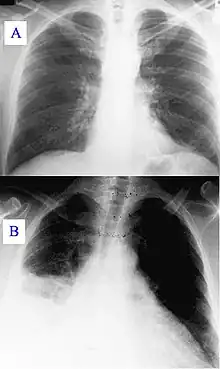

Image A: A normal chest X-ray Image B: Q fever pneumonia